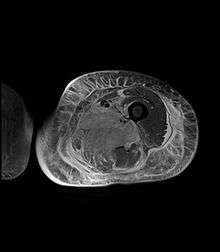

Axial fat suppressed post gadolinium contrast enhancement MRI image showing absent enhancement in the left thigh adductor muscles centrally indicating necrosis in diabetic myonecrosis.